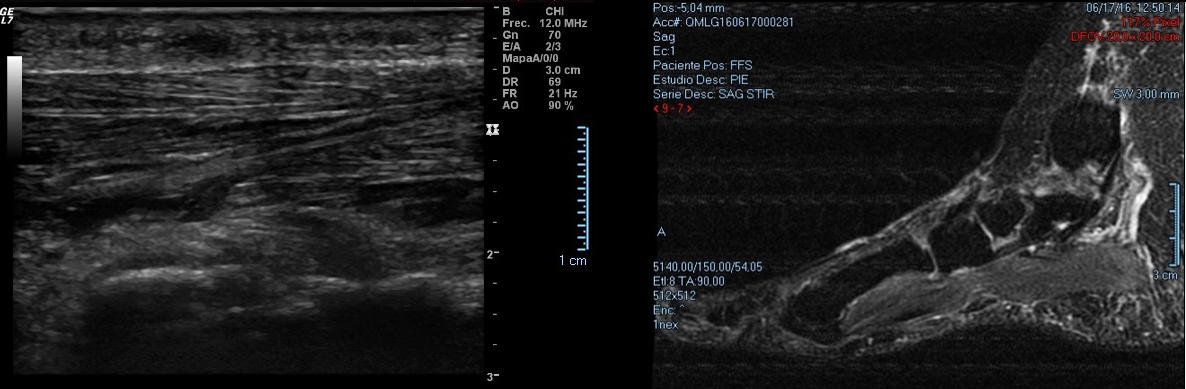

En general se pueden diagnosticar mediante la exploración clínica y una correcta anamnesis. A su vez nos apoyaremos en ecografías o RMN para visualizar la masa fusiforme, delimitar el grosor y diferenciar estructuras afectadas. A nivel de la zona dolorosa se puede apreciar una formación fusiforme de 15 mm hipoecogénica adyacente a la fascia plantar